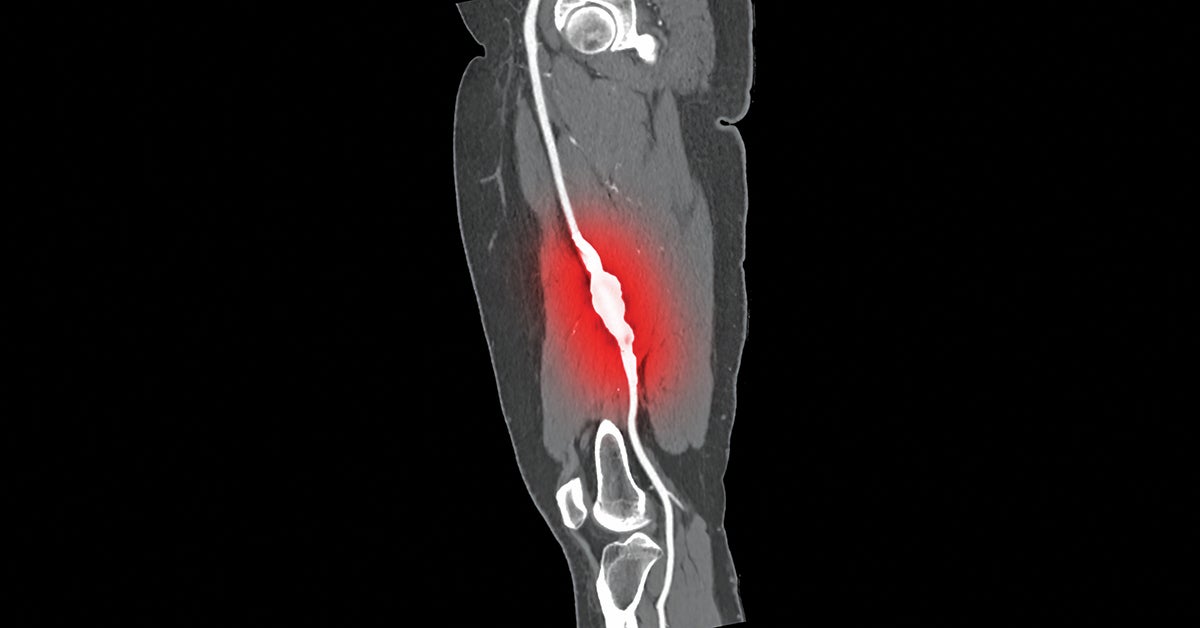

Lower limb amputations are on the rise nationally, a trend related to the aging of the population and the prevalence of diabetes and peripheral arterial disease (PAD). A new multidisciplinary program at Lehigh Valley Heart and Vascular Institute aims to counter this trend by quickly triaging people with limb-threatening conditions to optimum appropriate care.